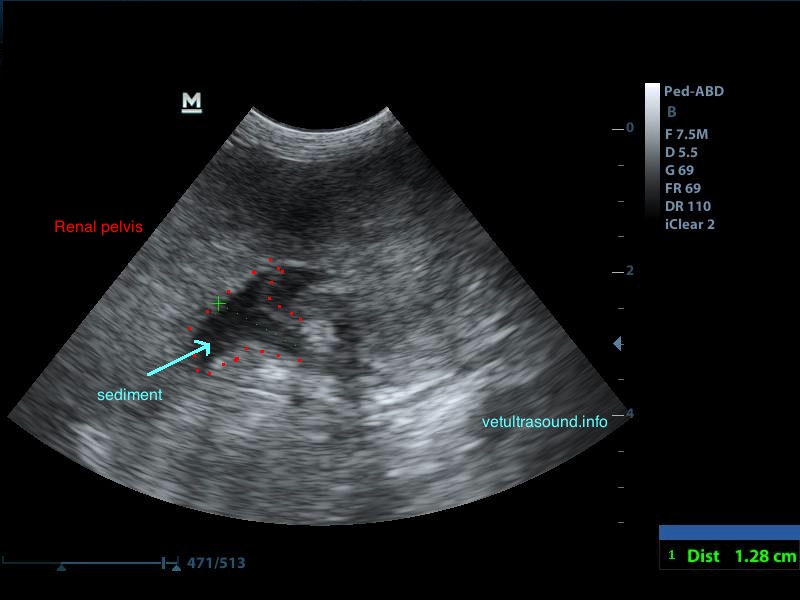

Ευρήματα: Στον υπέρηχο κοιλίας βρέθηκε επώδυνη διόγκωση και των δύο νεφρών με πάχυνση της φλοιώδους ουσίας, η οποία παρουσίαζε έντονη ανομοιογένεια. Οι νεφρικές πύελοι ήταν ήπια διατεταμένοι και στο εσωτερικό τους παρατηρήθηκε αφθονία ιζήματος. Οι ουρητήρες, οι οποίοι ήταν επίσης διατεταμένοι, απεικονίζονταν μέχρι την είσοδό τους στην ουροδόχο κύστη. Αφθονία ιζήματος βρέθηκε στην ουροδόχο κύστη. Η εικόνα αυτή είναι συμβατή με διάμεση νεφρίτιδα και στην συγκεκριμένη περίπτωση με πυοκοκκιωματώδη φλεγμονή των νεφρών, συνεκτιμώντας τα εργαστηριακά ευρήματα, τον έντονο πόνο και τη διάταση των ουρητήρων. Το resistive index ( δείκτης αγγειακής αντίστασης) βρέθηκε αυξημένο (0.77) σε μεσολόβιο αρτηρίδιο του νεφρού. Φυσιολογικά θα έπρεπε να είναι (0.6±0.06). Αυτό δείχνει πως το οίδημα του νεφρικού παρεγχύματος εξαιτίας φλεγμονής ή οποιαδήποτε άλλης διήθησης, νεοπλασματικής ή μη, πιέζει τα αγγεία και αυξάνει την αντίσταση του αίματος προς το νεφρό. Ένα επιπλέον διαγνωστικό βήμα για την διερεύνηση της αιτίας, για την αποτελεσματικότερη θεραπεία και την εγκυρότερη πρόγνωση, είναι η λήψη κυτταρολογικού υλικού από το νεφρικό παρέγχυμα και ούρου από τη νεφρική πύελο για καλλιέργεια, στα οποία ο ιδιοκτήτης δεν θέλησε να προχωρήσει.